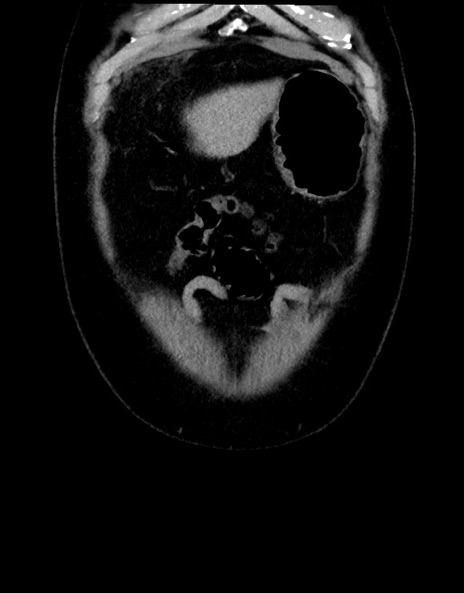

症例15(冠状断像)

【症例】70歳代男性

【主訴】腹痛

【現病歴】今朝から腹痛あり。全体的に痛い。特に左上の方。排ガスが今日はない。冷や汗が出る。

【既往歴】直腸癌術後

【身体所見】左側腹部〜上腹部に圧痛あり。腹膜刺激症状明らかなではない。軽度反跳痛。左下腹部に術後瘢痕あり。

【データ】WBC 7700、CRP 0.02